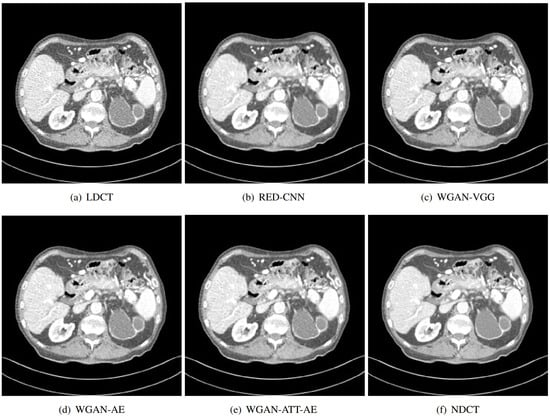

Figure 10 and Figure 11 illustrate the experimental results of our study on noise reduction in LDCT images using different methods. Figure 10 presents a side-by-side comparison of abdominal CT scans processed using different noise reduction methods. It includes (a) LDCT, (b) RED-CNN, (c) WGAN-VGG, (d) WGAN-AE, (e) WGAN-ATT-AE, and (f) NDCT. The WGAN-ATT-AE method shows a superior reduction in noise compared to other methods, closely approaching the quality of the normal dose CT. This is evident in the clearer visualization of anatomical structures. WGAN-ATT-AE maintains a high level of detail, similar to NDCT, while effectively reducing noise, unlike LDCT, which retains significant noise. Comparison with other methods: Compared to RED-CNN and WGAN-VGG, WGAN-ATT-AE and WGAN-AE provide better balance between noise reduction and detail preservation. WGAN-ATT-AE offers the most visually coherent and detailed image among the tested methods.

Figure 10.

Comparison of LDCT image denoising results using different methods.

Figure 11.

Comparison of local magnification of low-dose CT image denoising results using different methods.

The proposed WGAN-ATT-AE method demonstrates superior performance in both noise reduction and detail preservation, as seen in the overall comparison and the enlarged view. This visual evidence suggests that WGAN-ATT-AE is highly effective for enhancing the quality of LDCT images, potentially improving diagnostic accuracy while maintaining the advantages of low radiation exposure. These visual comparisons highlight the significant improvements achieved by our proposed method in terms of noise reduction and image quality enhancement, making it a promising tool for clinical applications in LDCT imaging.

Figure 11 shows an enlarged view of a specific region from the same set of abdominal CT scans used in the first image, focusing on the details provided by each method. The region in the LDCT image shows a significant amount of grainy noise, which obscures finer details and makes it difficult to interpret anatomical structures accurately. While RED-CNN reduces some noise, it still leaves a considerable amount of granularity, and some details are smoothed out. The WGAN-VGG method reduces noise effectively but introduces a slight blurring, which could affect the clarity of fine structures. This method provides a clearer image than the previous methods, with better detail retention and reduced noise. Our proposed method shows the best performance, significantly reducing noise while preserving fine details and textures, closely matching the quality of the NDCT. As the ground truth, the NDCT image presents the highest quality with minimal noise and clear anatomical details.

We conducted qualitative and quantitative analysis, and we compared the effects of the proposed methods (WGAN-AE, WGAN-ATT-AE) and the baseline method (WGAN-VGG) on locally enlarged images. The results show that the important anatomical structure and detailed information in the image can be effectively maintained while reducing noise, while the baseline method shows a greater degree of information loss. This finding further validates the superiority of the proposed method in maintaining image quality and highlights its potential application value in clinical diagnosis. The proposed method can better maintain detail information and structural integrity in locally enlarged images, and presents a clearer and more accurate enlargement effect compared with baseline methods. This finding highlights the superiority of the proposed method in image enhancement and provides more reliable support for clinical diagnosis, providing a further comparison of the performance of different methods in preserving image details and structure.